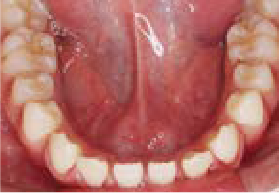

上の前歯がゆがみ下の歯が内側に傾いています。舌の位置が悪く、口を開けたまま食べ物を飲み込む癖がありました。また、口をポカンと開けてテレビを見ていることが多いなど、鼻づまりによる口呼吸特有の症状が見られました。

治療を終えて

装置によって上あごを広げ前歯をきれいに並べました。下の歯の位置も整えました。歯がしっかりと咬み合うようになり、舌の位置や鼻の通りも良くなりました。気道も広がったことで、口呼吸が改善されました。

主訴・治療内容 でこぼこの歯で、将来の歯並びが心配と来院されましたが、呼吸法やお口の使い方が原因と、丁寧に説明させていただきました。